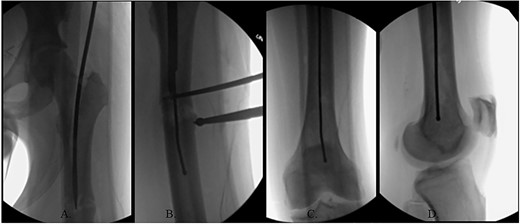

(A) Canulated cutter tool creating a new path in the proximal femur; (B) rigid canulated reduction rod directing the guidewire across a reduced fracture held with a proximal bone hook and distal ball spike pusher; (C) center positioned ball-tipped guidewire at the knee on the AP XR; (D) center positioned ball-tipped guidewire at the knee on the lateral XR.

The ball-tipped guidewire was extracted, and a sharp cannulated cutter created a novel path in the proximal segment (Fig. 4A). A rigid nonunion reamer (DePuy Synthes©, Raynham, MA) was advanced to widen the canal. Closed reduction was lost and so a lateral incision was made at the level of the fracture and a percutaneous reduction was achieved through use of a proximal bone hook and distal ball spike pusher (Fig. 4B).

The hip was extended, and a ball-tipped guidewire was successfully passed across the fracture site to a center–center positionwithin the canal at the level of the knee (Fig. 4C and D). Sequential 0.5-mm reaming from 9 to 13 mm prepared for an 11 × 400 mm, 125° Gamma3® intertrochanteric rod (Stryker© Kalamazoo, MI), with a 95-mm cephalomedullary screw and ×2 distal lateral to medial interlocking 5.0-mm screws (Fig. 5A–D). Through the course of the procedure, 400 cc of blood loss necessitated two units of packed red blood cells.